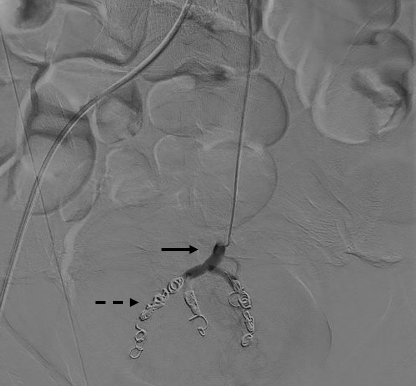

Super-selective catheterization of the superior rectal artery was done with a Renegade STC microcatheter (Boston Scientific) and a Fathom-16 steerable guidewire (Boston Scientific) (Figure 2), followed by superselective catheterization of the branches of the superior rectal artery. Embolization of the branches was performed in their middle and distal thirds with Interlock-18 controlled-release fiber microcoils (Boston Scientific), 1 to 2 units per branch. See Figure 3 for control angiography demonstrating branch occlusion.